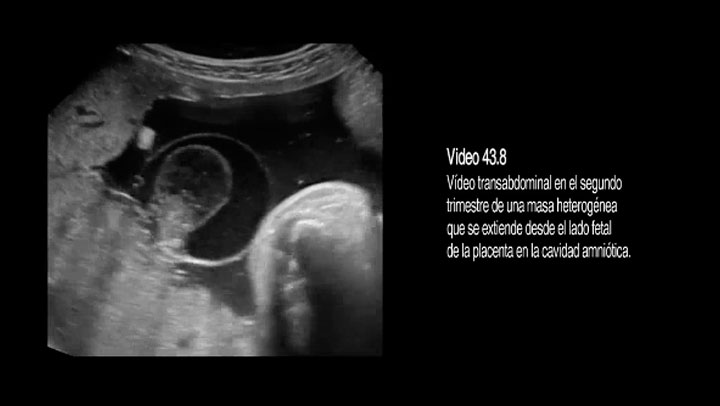

Video 43.08 Hematoma preplacentario